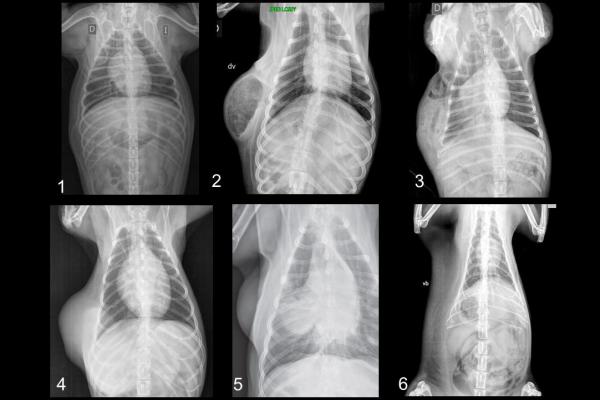

En la práctica clínica de todos los días, son muchas las especialidades que tienen a la radiología como un pilar del diagnóstico complementario. El método radiológico aporta información sobre la patología osteoarticular de huesos largos, columna y cráneo, enfermedades del aparato digestivo, renal, urinario y reproductor, el sistema respiratorio y cardiovascular.

Clase 1: Aspectos físicos básicos de los rayos X: Equipamiento radiológico. Formación de la imagen. Factores que determinan la definición, el contraste y la forma. Incidencias ortogonales. Nomenclatura.

Clase 14: Radiología abdominal: Incidencias. Preparación abdominal. División radiológica del abdomen. Contraste propio. Peritonitis focal y generalizada, carcinomatosis, masa. Neumoperitoneo. Retroneumoperitoneo.

Clase 15: Radiología hepatobiliar: lobulación. Tamaño: hepatomegalia. Microhepatia. Calcificación. Colecistitis enfisematosa. Litiasis vesicular. Nociones de colecistografía. Radiología esplénica: forma, tamaño y posición normal. Esplenomegalia generalizada y focal. Torsión esplénica. Radiología del páncreas: anatomía radiológica. Pancreatitis. Neoplasia. Radiología adrenal: anatomía radiológica. Adenomegalia. Calcificación. Radiología de los linfonódulos abdominales. Identificación sistemática de masas abdominales.

Clase 25: Radiología torácica general 1. Técnica radiológica y principales defectos técnicos. Anatomía radiológica general del tórax (continente y contenido). Principales afecciones del diafragma, pared costal y esternón. Radiología del mediastino: variaciones normales. Principales linfonódulos mediastínicos (craneales, esternal, perihiliares). Linfoadenomegalias. Diagnóstico diferencial de masa pulmonar. Neumomediastino.Información adicional